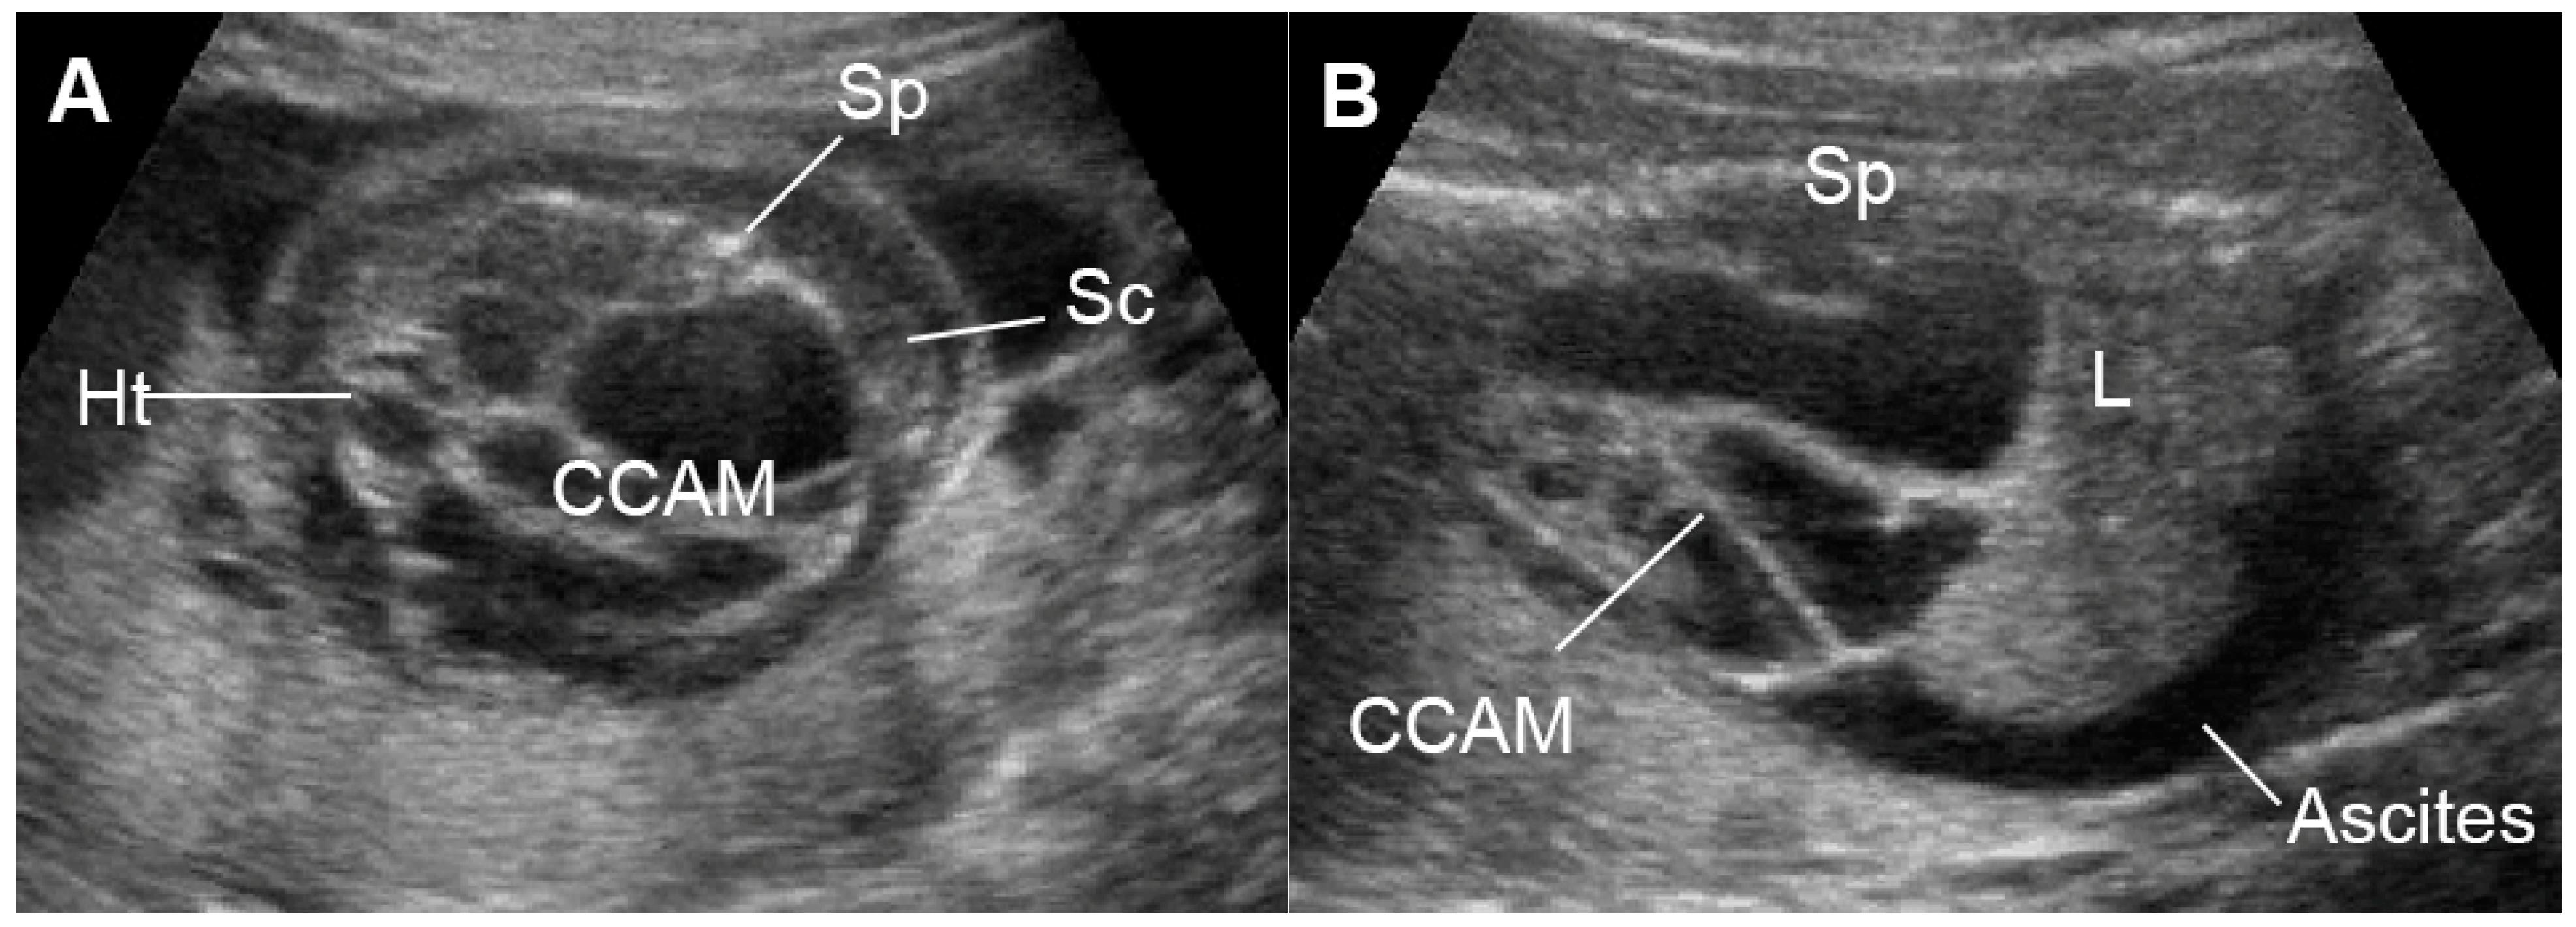

5.7.3. External Cardiac Compression

- Soni, S.; Moldenhauer, J.S.; Rintoul, N.; Adzick, N.S.; Hedrick, H.L.; Khalek, N. Perinatal Outcomes in Fetuses Prenatally Diagnosed with Congenital Diaphragmatic Hernia and Concomitant Lung Lesions: A 10-Year Review. Fetal Diagn. Ther. 2020, 47, 630–635. [Google Scholar] [CrossRef]

- Kane, S.C.; Da Silva Costa, F.; Crameri, J.A.; Reidy, K.L.; Kaganov, H.; Palma-Dias, R. Antenatal assessment and postnatal outcome of fetal echogenic lung lesions: A decade’s experience at a tertiary referral hospital. J. Matern. Fetal Neonatal Med. 2019, 32, 703–709. [Google Scholar] [CrossRef]